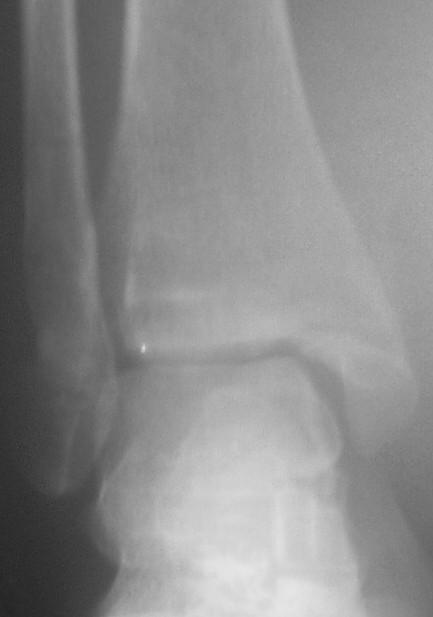

Трехчетвертной контрлатеральный

На боковом довольно неплохой сустав, скудная информация о положении вилки сустава при косой рентгенограмме (Mortise view) из-за положения стопы во внутренней ротации и эквинуса во время ренгенограммы.

Рекомендуемая реконструкция: удлинение малоберцовой с исправлением ротации, исправление внутренней лодыжки с фиксацией и фиксация синдесмоза через пластины, по моему уменьшат болевой синдром у этой больной.